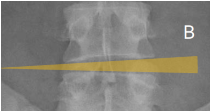

Q what is the name of this measurement? and what is the average + range?

Lateral Bending Sign

assesses segmental convergence toward the bending side during lateral flexion/side-bending (SB).

Each transverse line should increasingly converge toward the bending side from the lumbosacral (LS) junction upward. No average or range is specified.